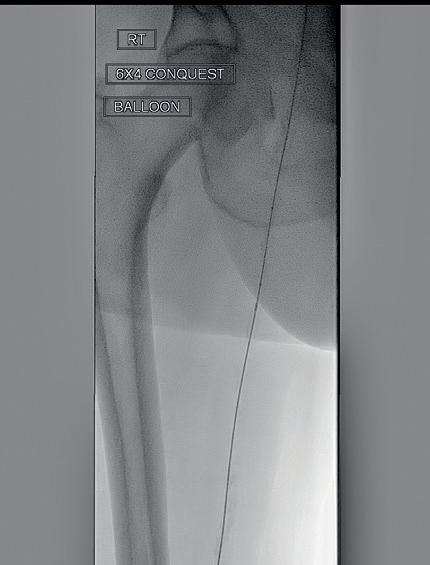

PERIPHERAL IVL

Shockwave Peripheral IVL: Reliably safe. Predictably effective. Backed by real-world and level one evidence, Shockwave IVL modifies both superficial and deep calcium. Designed for the iliacs, fem-pop and below-the-knee arteries, these purpose-built devices come in sizes that allow you to treat calcium at any level. So you can count on affecting outcomes for the better.

Peripheral Important Safety Information

In the United States: Rx only.

Indications for Use—The Shockwave Medical Intravascular Lithotripsy (IVL) System is intended for lithotripsy-enhanced balloon dilatation of lesions, including calcified lesions, in the peripheral vasculature, including the iliac, femoral, ilio-femoral, popliteal, infra-popliteal, and renal arteries. Not for use in the coronary or cerebral vasculature.

Contraindications—Do not use if unable to pass 0.014” (M5, M5+, S4) or 0.018” (L6) guidewire across the lesion-Not intended for treatment of in-stent restenosis or in coronary, carotid, or cerebrovascular arteries.

Warnings—Only to be used by physicians who are familiar with interventional vascular procedures—Physicians must be trained prior to use of the device— Use the generator in accordance with recommended settings as stated in the Operator’s Manual.

Precautions—use only the recommended balloon inflation medium—Appropriate anticoagulant therapy should be administered by the physician—Decision regarding use of distal protection should be made based on physician assessment of treatment lesion morphology.

Adverse effects–Possible adverse effects consistent with standard angioplasty include–Access site complications –Allergy to contrast or blood thinner–Arterial bypass surgery—Bleeding complications—Death—Fracture of guidewire or device—Hypertension/Hypotension—Infection/sepsis—Placement of a stent—renal failure—Shock/pulmonary edema—target vessel stenosis or occlusion—Vascular complications. Risks unique to the device and its use—Allergy to catheter material(s)— Device malfunction or failure—Excess heat at target site. Prior to use, please reference the Instructions for Use for more

contraindications,

©2024 Shockwave Medical Inc. All rights reserved. SPL-70888 Rev A Learn more at ShockwaveMedical.com/Peripheral-IVL COUNT ON IT THE SOUND CALCIUM SOLUTION

information on indications,

warnings, precautions and adverse events. www.shockwavemedical.com/IFU